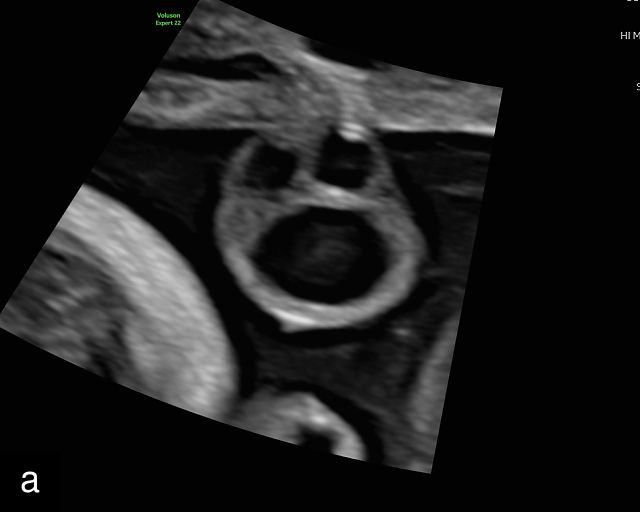

The umbilical cord serves as the lifeline connecting the fetus to the placenta. It arises from the midportion of the fetal abdomen and typically inserts into the center of the placenta (Figure 16). The average length of the umbilical cord is approximately 55 cm (22 inches).185 It contains three vessels: two arteries, which originate from the fetal left and right internal iliac arteries, and one vein, collectively referred to as a three-vessel cord.

16

Normal appearance of the umbilical cord with two umbilical arteries and a single vein. (a–c) Cross-section of the umbilical cord on grayscale (a,b) and power Doppler (c) ultrasound. In the normal cord, three vessels are visible: a larger umbilical vein and two smaller umbilical arteries. This characteristic appearance is often referred to as the 'Mickey Mouse' sign, the larger circle (umbilical vein) representing Mickey’s face while the smaller circles (arteries) form his ears. (d–g) Grayscale (d) and color Doppler (e–g) images of transverse section of the lower fetal abdomen showing the two umbilical arteries diverging around the fetal bladder. (h) Longitudinal ultrasound view with color Doppler of a normal umbilical cord showing three vessels present in each coil: two arteries with flow in one direction and a single vein with flow in the opposite direction.

At a minimum, the mid-trimester ultrasound should include identification and documentation of the umbilical cord's fetal and placental insertions, as well as the number of cord vessels.66,186,187 In a transverse grayscale section of the cord, the two umbilical arteries can be visualized alongside the larger, thinner-walled umbilical vein, creating a characteristic ‘Mickey Mouse’ appearance (Figure 16a–c). Additionally, in a transverse section of the lower fetal abdomen, the umbilical arteries are seen encircling the fetal bladder. This can be seen on grayscale ultrasound and confirmed with color flow Doppler (Figure 16d–g).